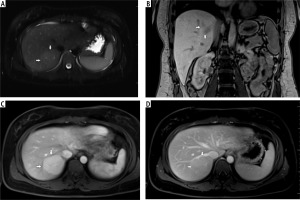

Fig. 2

A) T2-weighted image in transverse plane, focal lesion in the right lobe of the liver (full white arrows). Signal of the lesion slightly higher in relation to the liver parenchyma. B) T1-weighted image in coronal plane. Focal lesion in right lobe of the liver (full white arrows). The signal of the lesion is lower in relation to the liver parenchyma. In this sequence, the heterogeneity of the signal within the lesion is clearly visible. C) T1-weighted image in the early phase after administration of a contrast agent. Acquisition in the transverse plane. Focal lesion in the right lobe of the liver (full white arrows). The lesion enhances intensively in relation to the liver parenchyma. D) T1-weighted image in the late phase after administration of a contrast agent. Acquisition in transverse plane. Focal lesion in the right lobe of the liver (full white arrows). Enhancement of the lesion and the parenchyma of the liver in this phase is similar. The lesion was classified as hepatocellular adenoma (HCA)